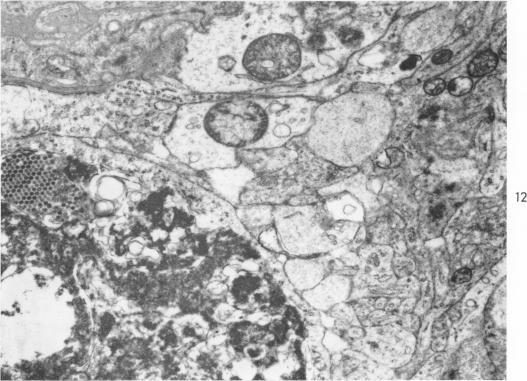

REOVIRUS ENCEPHALITIS IN NEWBORN MICE: AN ELECTRON MICROSCOPIC AND VIRUS ASSAY STUDY.

Am J Pathol. 1965 Aug;47(2):223-39.